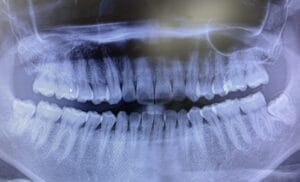

親知らずとは、永久歯の中で最後に生えてくる奥歯(第3大臼歯)のことです。正式には「第三大臼歯」と呼ばれ、上下左右あわせて一般的には最大4本あります。親知らずの本数は、歯科用レントゲンやCTで正確に確認できます。

特に埋伏している場合は、見た目では分からないことも多いです。

親知らずの痛みは、歯ぐきの炎症(智歯周囲炎)や、虫歯・歯の根の感染などが原因で起こることが多くあります。症状や親知らずの生え方は個人差が大きいため、レントゲン検査を行い、歯や骨の状態を正確に確認した上で診断します。

きらら歯科ではCTを完備しており、親知らずの状態を立体的に確認したうえで、安全性に配慮した診断・抜歯を行っています。